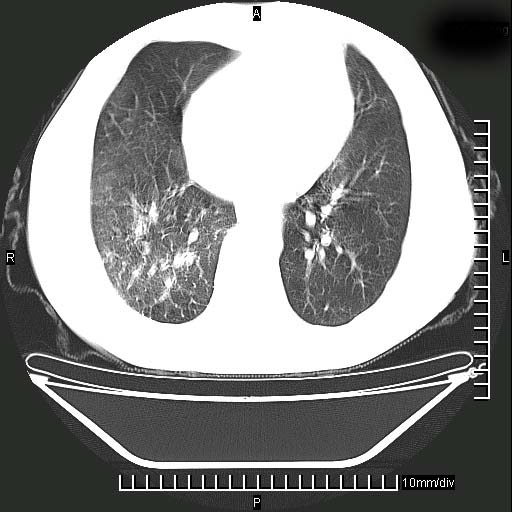

标题: CT24043:胸部增强:男性,60岁

既往肺结核,近10几天,咳嗽,咳痰,右侧胸痛,疼痛较明显,右上肺斑块考虑结核灶胸膜粘连,增强,可惜动脉期没有定好,未见强化,可延迟4分后又见较明显强化,中心见低密度影,如果说结核是边缘强化,可这个灶强化的面积挺大的,让人很挠头。

动脉期

1)两肺继发性肺结核。2)右侧胸膜增厚+少量胸腔积液。